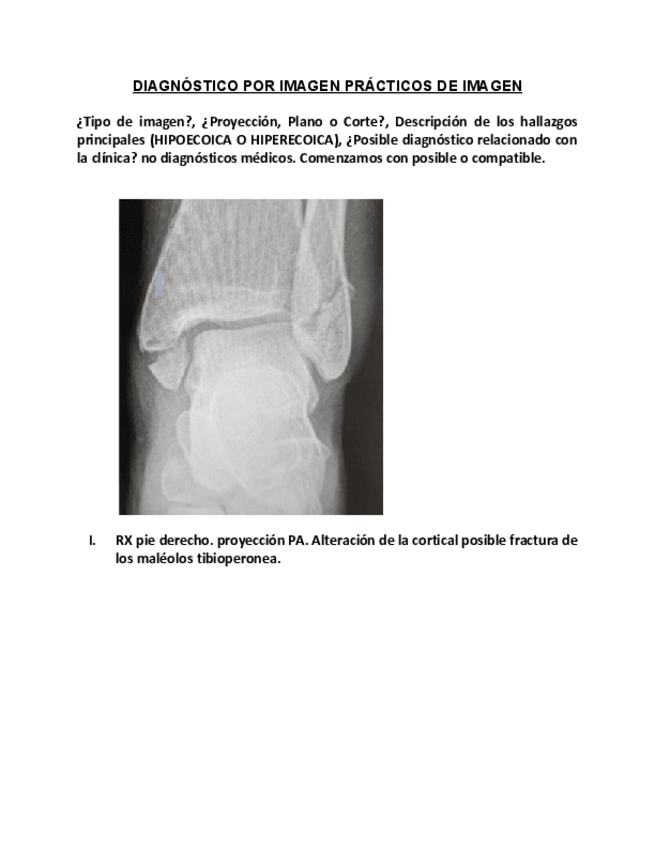

IMAGENES CORREGIDAS